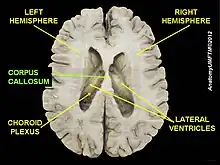

It is suggested that the underdevelopment or lack of white matter in the developing fetus could be a cause of colpocephaly. The partial or complete absence of white matter, also known as agenesis of the corpus callosum results in anatomic malformations that can lead to colpocephaly. This starts to occur around the middle of the second month to the fifth month of pregnancy. The lateral ventricles are formed as large cavities of the telencephalic vesicle. The size of the ventricles are decreased in normal development after the formation of the Foramen of Magendie, which decompresses the ventricular cavities. Myelination of the ventricular walls and association fibers of the corpus callosum and the calcarine fissure helps shape the occipital horns. In cases where this developmental process is interrupted, occipital horns are disproportionately enlarged.[4]

Colpocephaly is characterized by disproportionately large occipital horns of the lateral ventricles (also frontal and temporal ventricles in some cases). MRI and CT scans of patients demonstrate abnormally thick gray matter with thin poorly myelinated white matter. This happens as a result of partial or complete absence of the corpus callosum. Corpus callosum is the band of white matter connecting the two cerebral hemispheres. The corpus callosum plays an extremely important role in interhemispheric communication, thus lack of or absence of these neural fibers results in a number of disabilities.[12]

Stem cell therapy is considered a very promising treatment for patients with colpocephaly. Oligodendroglial cells can be used which will increase the production of myelin and alleviate symptoms of colpocephaly. Damage to the developing oligodendrocytes near the cerebral ventricles causes cerebral palsy as well as other demyelinating diseases such as multiple sclerosis and leukodystrophies. Demyelination reduces the speed of conduction in affected nerves resulting in disabilities in cognition, sensation, and motor. Therefore, by using oligodendrocyte stem cells the effects of cerebral palsy can be treated and other symptoms of colpocephaly can be alleviated.[13]